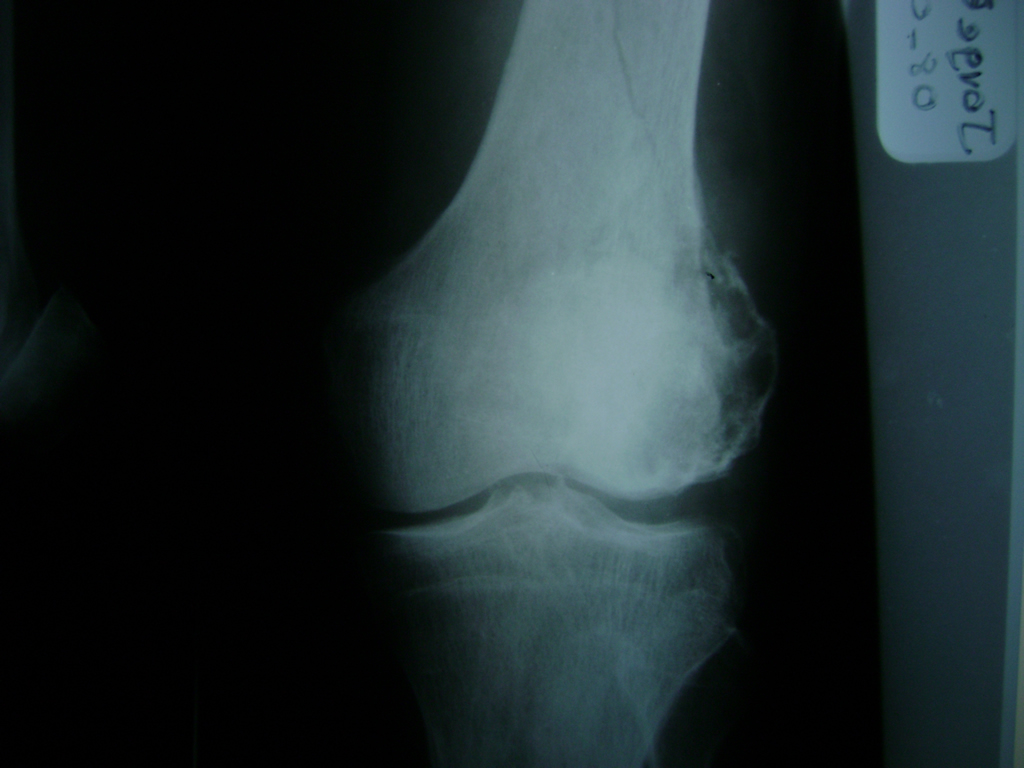

Cirugías de Rodillas

La artroscopia de rodilla es un cirugía en el cual la estructura interna de la articulación es examinada ya sea para realizar un diagnostico o para realizar un tratamiento, este procedimiento se realiza utilizando un instrumento parecido a un pequeño tubo llamado artroscopio.